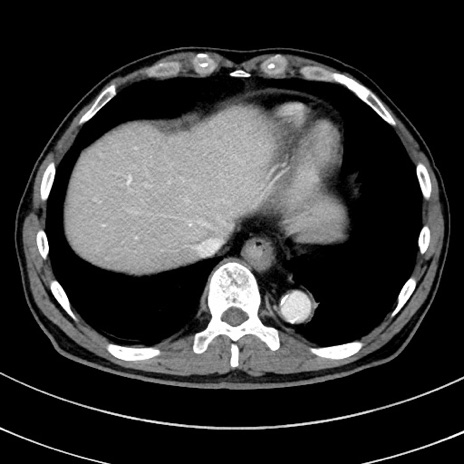

症例8(横断像)

【症例】 60歳代男性

【主訴】 黒色吐物

【現病歴】 4日前から嘔気自覚、2日前の朝食後にも嘔気あり、自分で手で嘔吐反射起こし嘔吐したところ血が混ざっていたため受診。

【既往歴】 5年前汎発性腹膜炎を伴う急性虫垂炎で手術、高血圧、前立腺肥大症、高脂血症

【身体所見】 腹部正中に手術癩痕あり 腹部平坦・軟圧痛なし膨満感あり

【データ】WBC 8400、CRP 4.54